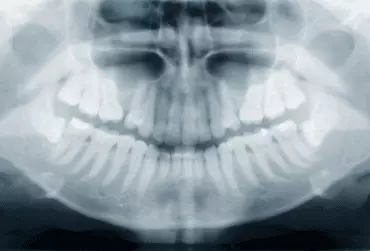

W codziennej praktyce stomatologicznej lekarz spotyka się także z pacjentami, u których jest zmuszony do usunięcia zębów w odcinku przednim i nierzadko są to przypadki nagłe. Metodą z wyboru powinna być wtedy implantacja natychmiastowa i o ile to możliwe – z natychmiastowym obciążeniem.